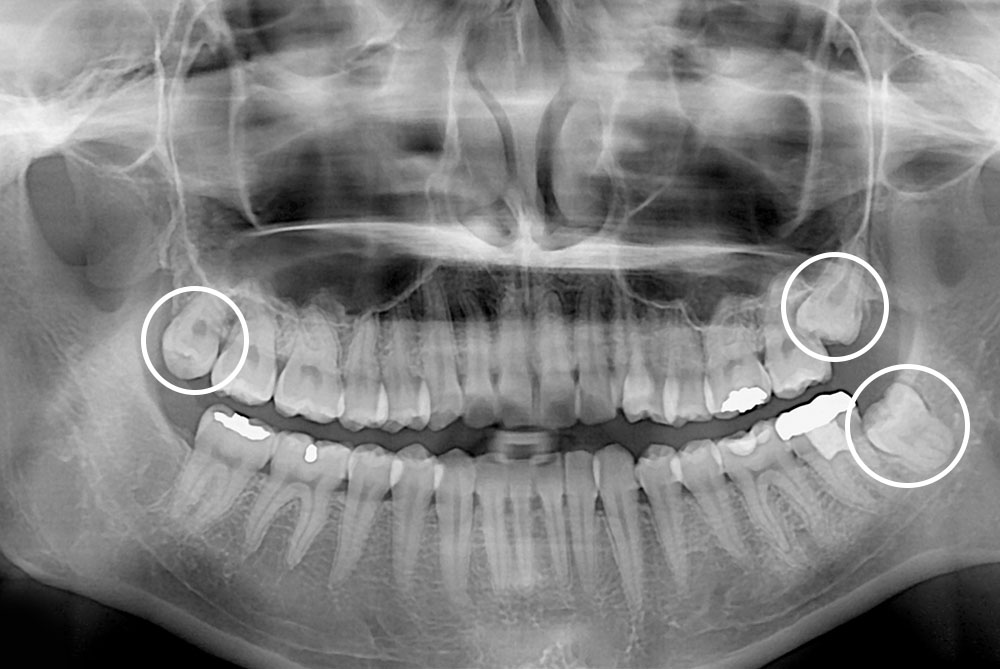

[사랑니] 매복 사랑니 발치

치료후 : 2022-07-28

세종치과는 구강악안면외과학 박사이신 원장님이 발치하는 치과입니다.